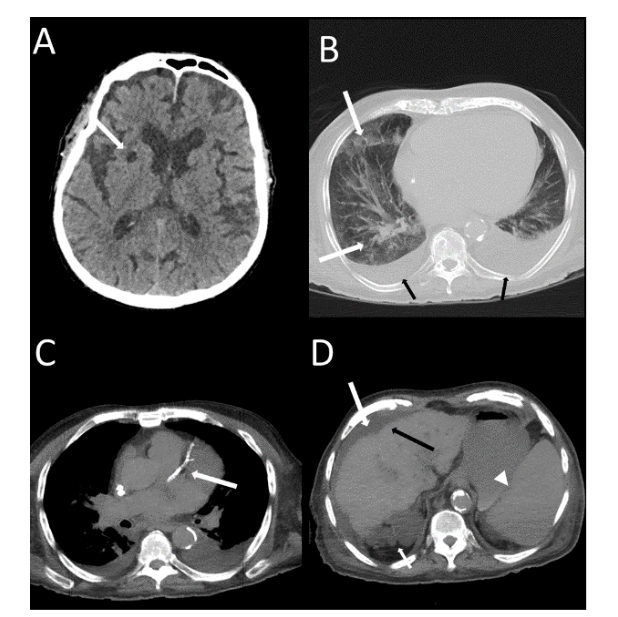

A greater frequency of deaths was found in males compared to females without statistical significance. However, the patients who died (Figure 2 and 3) with statistical significance were older and more frequently presented systemic arterial hypertension, diabetes mellitus, chronic kidney failure, dyspnoea, more than 50% extension pulmonary involvement and moderate-severe CACs or coronary arterial stent.

- Aragao MdFVV, Leal MdC, Andrade PHP, et al. Clinical and radiological profiles of COVID-19 patients with neurological symptomatology: a comparative study. Viruses. 2021;13(5):845. doi:10.3390/v13050845